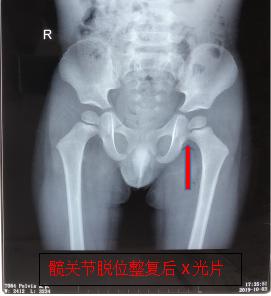

经过2分钟的中医正骨手法治疗后,下午17时35分,患儿复查X光检查结果出来了,骨伤六科医疗团队看到幼儿左髋关节脱位复位后关节位置结构正常,如释重负地松了一口气。

随后该团队细心交代患儿家属,复位后的患肢需予以外展、外旋位皮套牵引固定3-4周,患肢进行非负重主动及被动功能锻炼,2-3个月后逐渐恢复负重及行走;并不厌其烦地嘱咐患儿家属,除了要定时门诊复诊外,如遇到不适需及时复诊,以及日常护理等相关注意事项。该团队表示,会密切随访患儿,确保孩子骨骼健康发育成长。